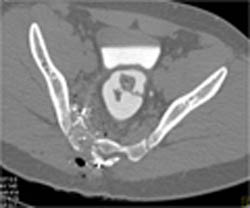

Diagnosis

Normal CTA